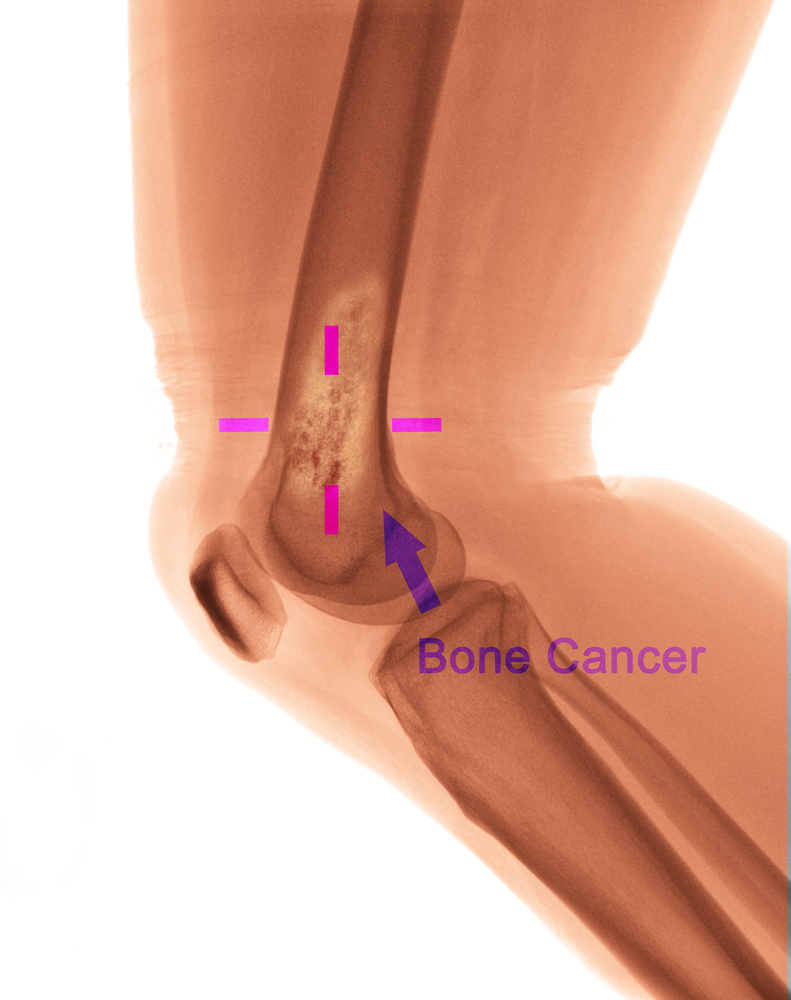

골암이란?

우리 뼈에도 양성종양은 모티론 악성종양의 암이 생길 수도 있어요. 뼈에 생기는 악성종양 중 가장 일반적인 원발성 암은 골육종(골종양)이라고 합니다. 골육종은 암 전체 중 0.2% 정도 밖에 없는 드문 암입니다. 우리나라에서는 연간 100명 정도 발생하고 있는 것으로 알려져 있습니다.

골암 증상

골암의 증상으로는 손발, 무릎의 통증이나 붓기, 부종, 시간이 지날수록 통증이 강해지고 진통제를 먹어도 낫지 않는 등의 증상이 있습니다.

문제는 이러한 골암증상을 단순히 성장통으로 오인하고 빠른 치료시기를 놓칠 가능성이 있다는 점입니다. 골육종은 인체 뼈의 어느 부위에나 발생할 수 있는데 무릎 통증, 골반 통증이 가장 빈번하게 발생하며 이로 인해 무릎 부위가 암에 가장 많이 발생합니다. 성장기 청소년들은 보통 많은 운동을 하고 활동적이어서 이렇게 무릎 통증이나 손발 통증, 부종 등이 나타나더라도 크게 신경 쓰지 않습니다.